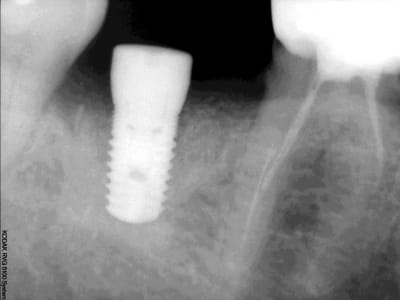

J'ai mis il y a de ca 1 mois 1 implant en position de 46 de 6 mm de diametre et de 8 mm de long car proche du nerf.

Au bout de 1 mois à la radio retroalveolaire je n'ai pas d'image qui me laisse penser un rejet ,ni meme de douleur.Mais l'implant bouge ?

peux tu nous mettre ta radio pour t'en dire un peu plus...

radiologiquement as tu un contact intime (petite fibrose asymptomatique pour le patient mais ton implant bouge) en fait on ne sait jamais quel pourcentage de la surface s'ostéointègre ...

quelle que soit nos considérations vu la longueur de l'implant tu pousse 1/3 de carpule et il va monter es tu sur de ne pas pouvoir mettre plus long ta rvg est franchement moyenne as tu utilisé l'export du logiciel kodak ?

d'accord avec chicot,remettre implant plus mesial,et d'apres les apexs des dents voisines tu peux en mettre un plus long

et le scan ? tu sembles avoir de la hauteur pourtant ?

> non c'est du 5 mm

il me semblait bien !!! pourtant tu avais dit du 6 mm !!!??? n'aurais-tu point sur-foré ?

qqch me dit que tu as été trop fort dans ton forage et avec du 8 de long ça ne pardonne pas...

de plus tu te dis proche du nerf mais ta radio montre que tu peux au moins mettre du 11,5 mm

tu vas donc redescendre à 10 mm de profond avec tes forêts pour un diamère crestal de 5 , bien gratter tes parois et poser un diamètre 6 par 11,5 par exemple, vis de fermeture, sutures.

A mon avis tu n'avais pas beaucoup de hauteur et une crete large, et ton implant est cratérisé tout autour et tu voi a la radio les corticales. dc radiologiquement ca va mais tu as une conque fibreuse autour